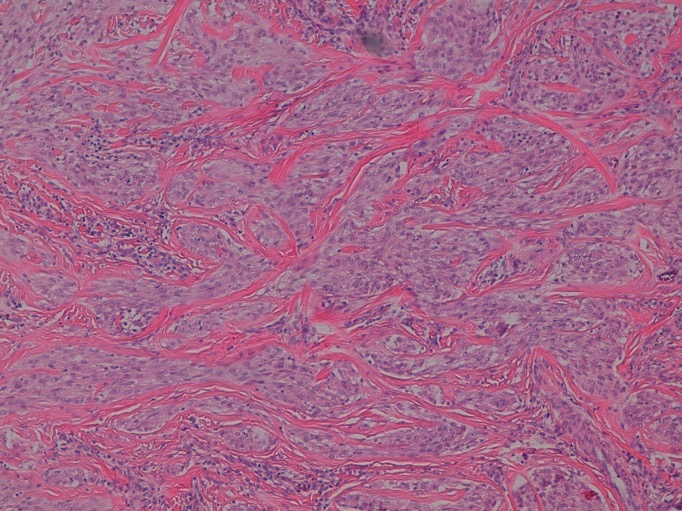

Neurothekeoma is a rare benign neoplasm of uncertain histogenesis. Progresses in immunohistochemistry have brought new insights into its cellular differentiation and origin, recognizing the possibility of a fibrohystiocitic lineage. Also, it has been subclassified histopathologically as either myxoid, cellular, or mixed type, depending on the amount of myxoid matrix and on immunohistochemical analysis. Few cases of cellular neurothekeoma have been reported. Most of them are found on the head, neck and upper extremities and mostly in young female adults. On review of literature we have not found reports regarding dermoscopic features of neurothekeoma. Herein we report an uncommon case of cellular neurothekeoma on the axilla of a 7–year-old girl, with description of its dermoscopic findings.

Hornick JL, Fletcher CD. Cellular neurothekeoma: detailed characterization in a series of 133 cases. Am J Surg Pathol. 2007;31:329-40.

Fetsch JF, Laskin WB, Hallman JR. Neurothekeoma: an analysis of 178 tumors with detailed immunohistochemical data and long-term patient follow-up information. Am J Surg Pathol. 2007;31:1103-14.

Jaffer S, Ambrosini-Spaltro A, Mancini AM, Eusebi V, Rosai J. Neurothekeoma and plexiform fibrohistiocytic tumor: mere histologic resemblance or histogenetic relationship? Am J Surg Pathol. 2009; 33: 905-13.

Barnhill RL, Dickersin GR, Nickeleit V, Bhan AK, Muhlbauer JE, Phillips ME, et al. Studies on the cellular origin of neurothekeoma: clinical, light microscopic, immunohistochemical, and ultrastructural observations. J Am Acad Dermatol. 1991;25:80-8.

Calonje E, Wilson-Jones E, Smith NP, Fletcher CD. Cellular 'neurothekeoma': an epithelioid variant of pilar leiomyoma? Morphological and immunohistochemical analysis of a series. Histopathology. 1992;20:397-404.

Misago N, Satoh T, Narisawa Y. Cellular neurothekeoma with histiocytic differentiation. J Cutan Pathol. 2003; 30:196-201.